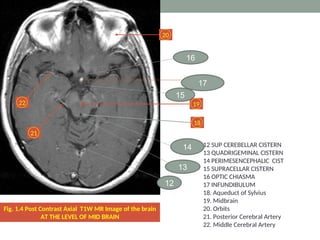

Fig. 1.4 Post Contrast Axial T1W MR Image of the brain

AT THE LEVEL OF MID BRAIN

12 SUP CEREBELLAR CISTERN

13 QUADRIGEMINAL CISTERN

14 PERIMESENCEPHALIC CIST

15 SUPRACELLAR CISTERN

16 OPTIC CHIASMA

17 INFUNDIBULUM

18. Aqueduct of Sylvius

19. Midbrain

20. Orbits

21. Posterior Cerebral Artery

22. Middle Cerebral Artery